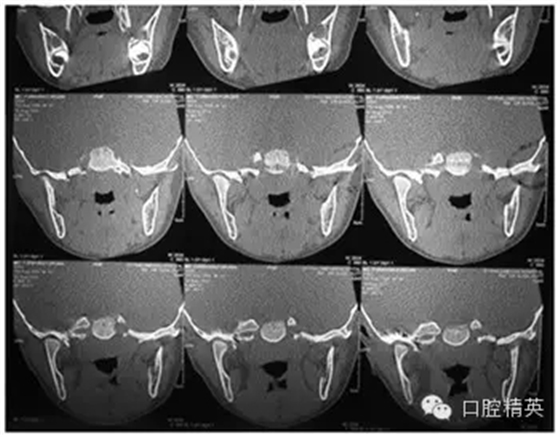

CT掃描圖像顯示,患者左顳下頜關節處呈現出大塊分頁狀組織影像,喙突前方軟硬組織影像分界不清晰(圖2,圖3)。血液檢測結果顯示患者各項生化指標正常。最后,工作人員用聽力測試評估了患者的耳朵功能是否已經受到腫瘤影響。

2 左顳下頜關節處異常的組織影像

3 喙突前方軟硬組織影像分界模糊